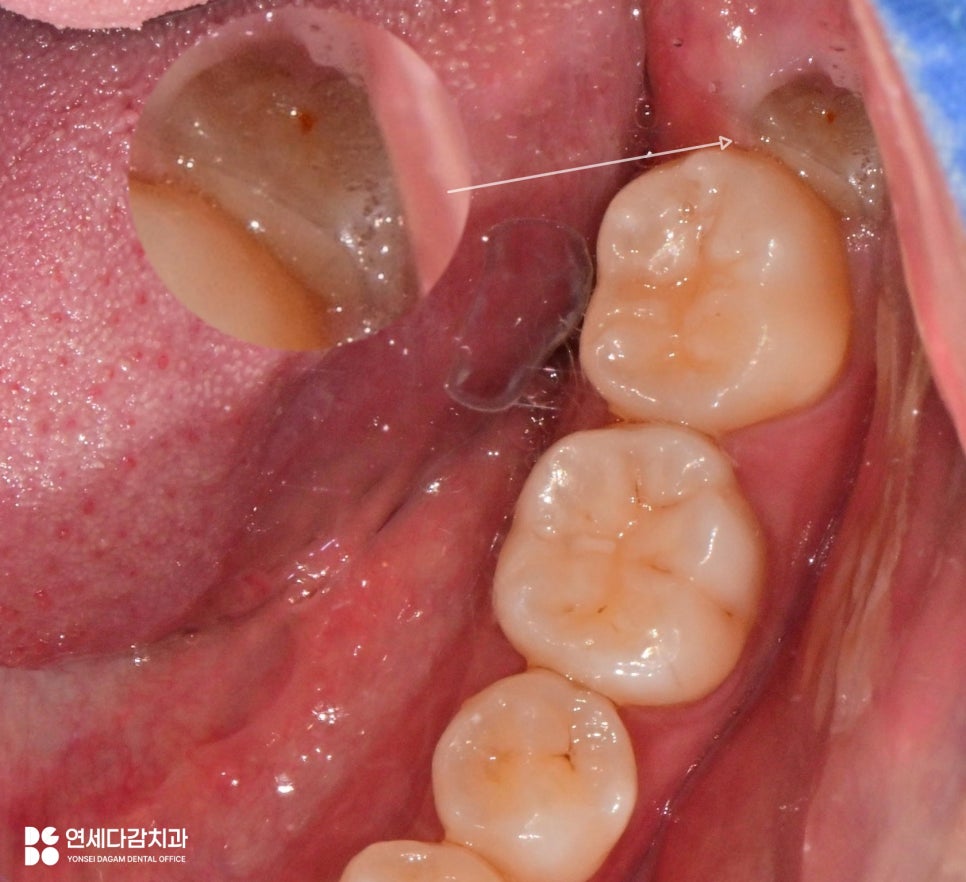

앞쪽(근심)부분은 밖으로 나왔지만,

뒤쪽(원심)은 잇몸 속에 묻혀 있습니다.

이를 오금역 치과 에서 평가했을 때

후방으로 경사진 형태로 짐작됩니다.

지금처럼 치관이 제대로 나오지 못한 경우

앞어금니와의 사이에 공간이 형성되어

음식물과 세균은 쉽게 들어갑니다.

반면 칫솔질이 제대로 되지 않는

청결의 사각지대가 만들어집니다.